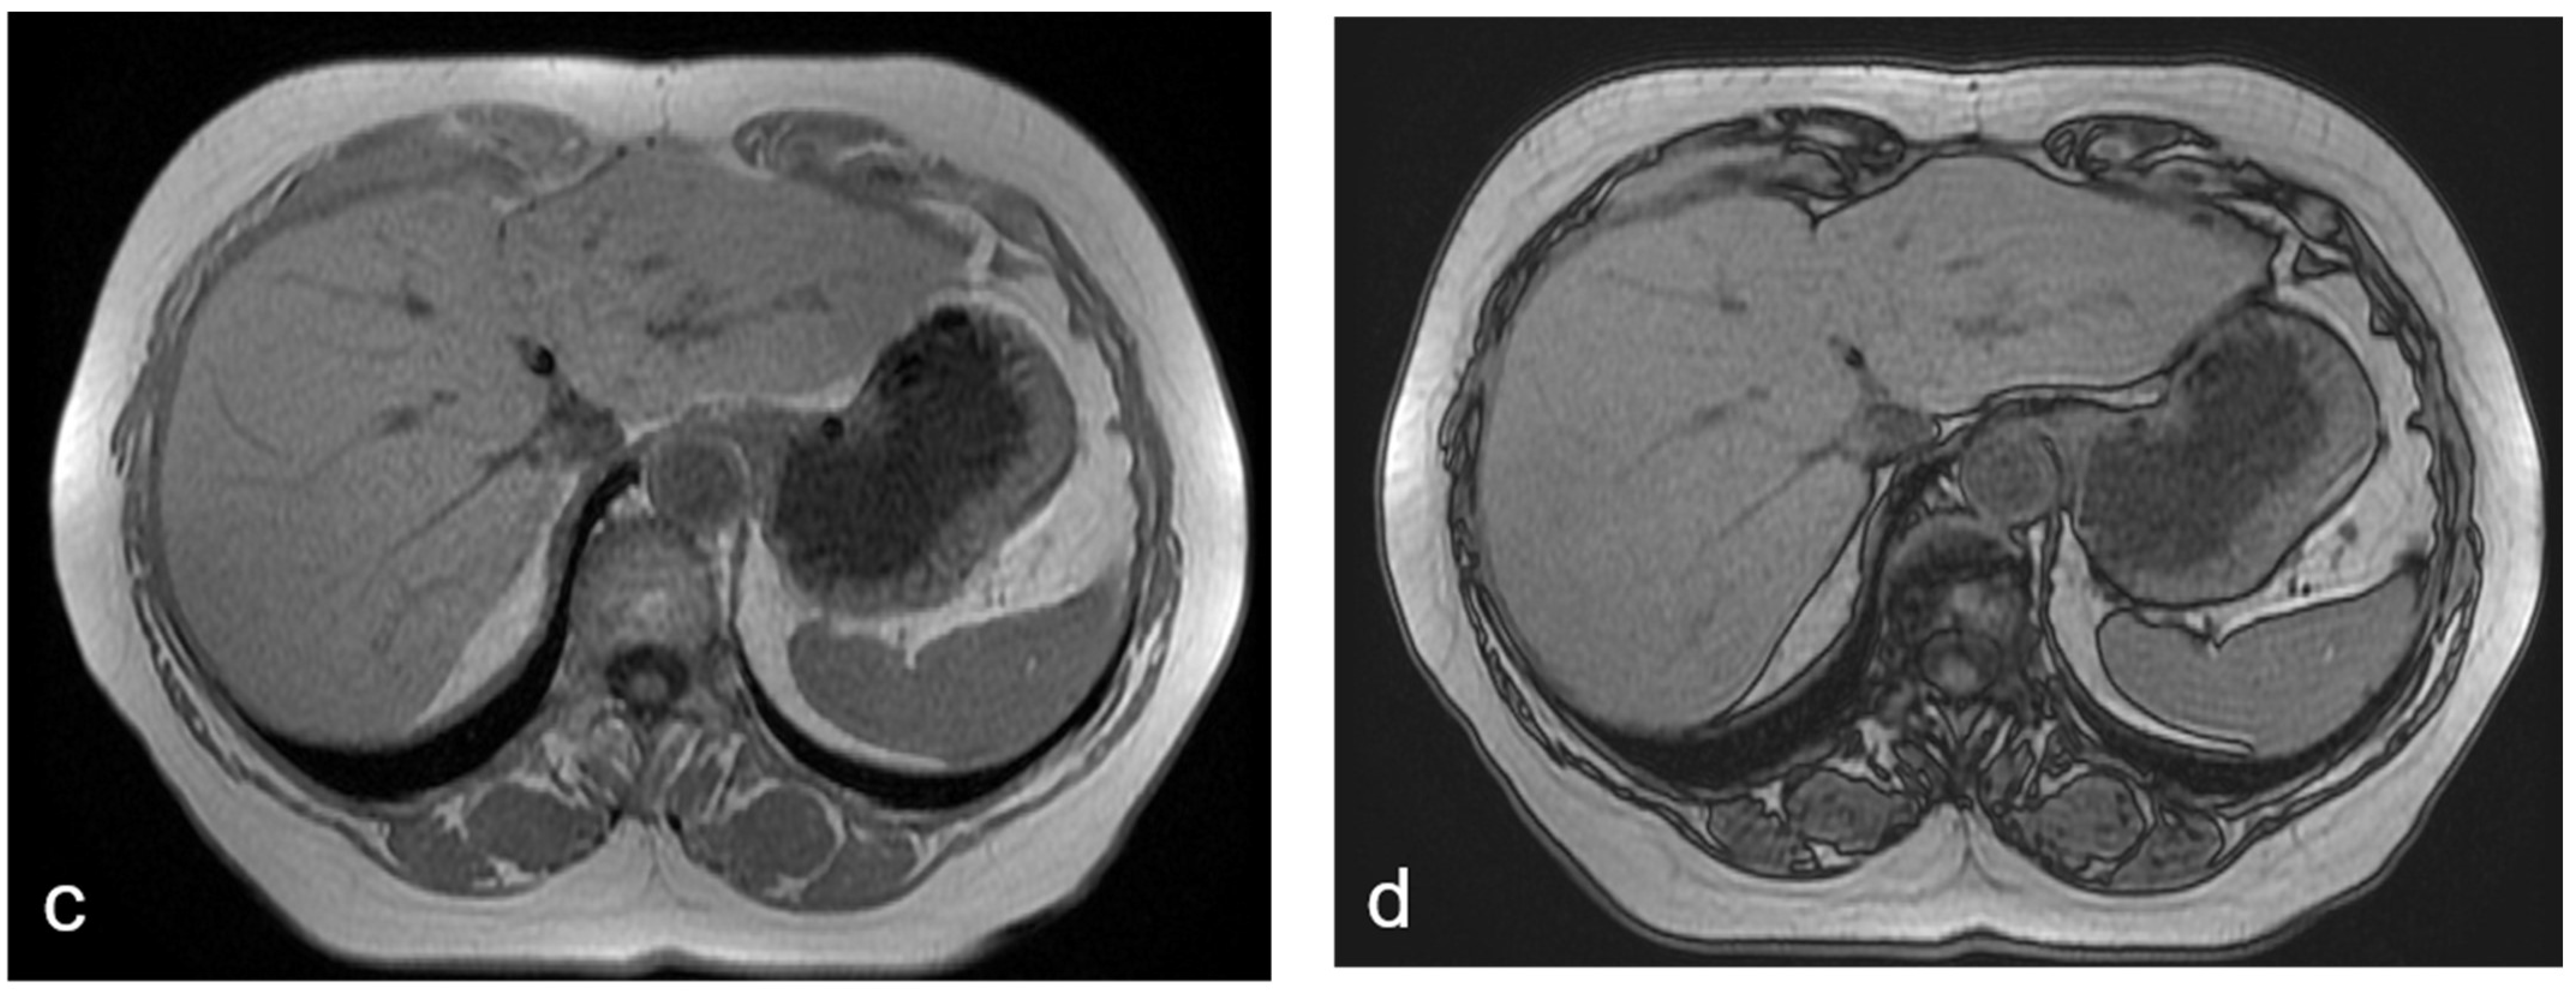

Figure 1.

(a–d) A 68-year-old woman with liver metastases from colon cancer undergoing neo-adjuvant chemotherapy with 5-fluoroacil and irinotecan (FOLFIRI). After chemotherapy, the axial T1-weighted in-phase image (a) showed diffuse hyperintensity of the liver with two adjacent hypointense metastatic lesions in segment 4, and the axial T1-weighted opposite-phase image (b) demonstrated a loss of signal at the level of the non-tumoral-bearing liver parenchyma, suggesting hepatic steatosis; moreover, the metastatic lesions appeared bright relative to the steatostic liver. About a year after the last chemotherapy and after resection of liver metastases, on MRI, no differences were found in the signal intensity between the axial T1-weighted in-phase image (c) and opposite-phase image (d) at the level of the liver parenchyma; therefore, we deduced that the steatosis was resolved.